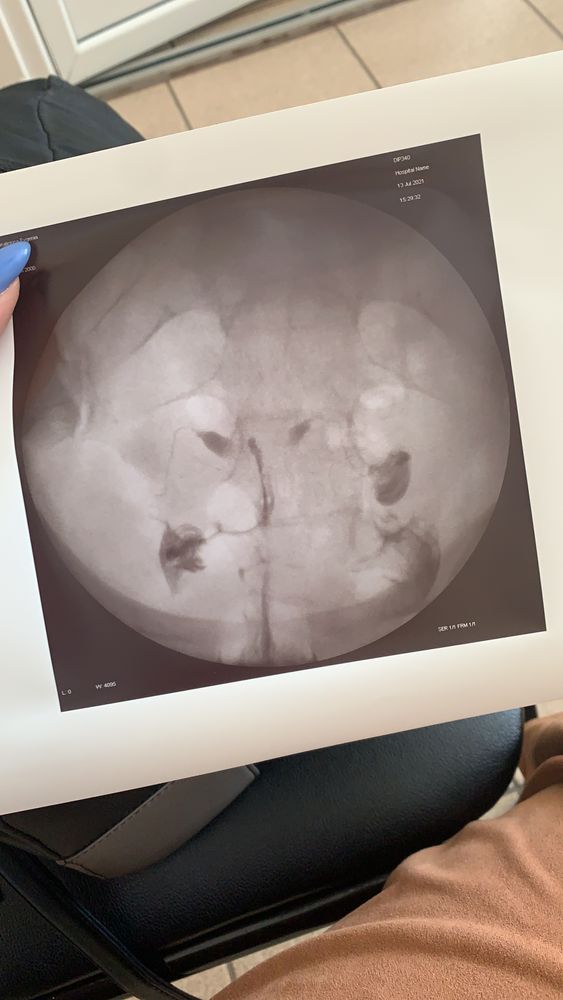

Результат гсг!)

Девочки , кто опытнее или разбирается , посмотрите снимок!) кажется две трубы проходимы?! Доктор , которая делала гсг сказала все ок! Лечащий доктор сказала , что ей не очень нравится нужна лапара! Третий доктор вообще загнул, что у меня аномалия развития удвоение матки или что-то такое 🙄 где истина ? Не хочу идти на лапару ,но и как понимаю , стимулировать без лапары меня не будут 🤯

Мама офтальмолог , я делала по ОМС и на руки не дают описаний , все в карте у доктора) но после процедуры доктор , которая делала , затем смотрела снимки и описывала, и сказала все хорошо, трубы проходимы , а моя в том же центре через 10 минут посмотрела и сказала что сомневается в проходимости